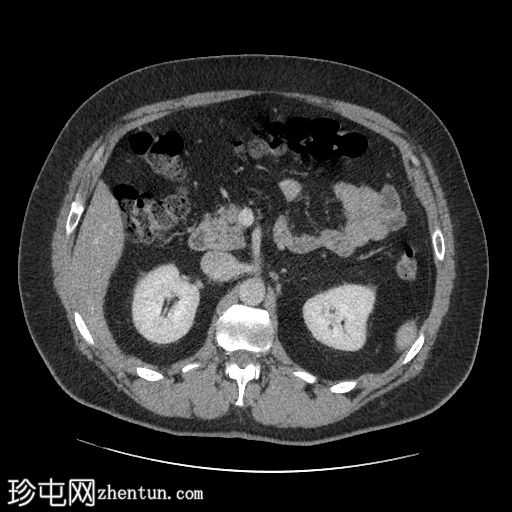

CT

轴位增强扫描(门静脉期)

左髂前窝可见一卵圆形局灶性腹膜内脂肪条索影,周围环绕一薄层高密度环。

影像

表现符合大网膜梗死。

脂肪密度影大于3.5 cm提示大网膜梗死而非大网膜垂炎。然而,这两种情况均属于良性、自限性腹膜内局灶性脂肪梗死的范畴,无需手术干预。